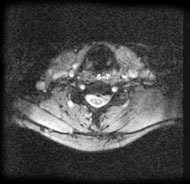

Axial magnetic resonance image of the cervical spine. This image reveals a C6-C7 herniated nucleus pulposus.

- MRI has become the method of choice for imaging the neck to detect significant soft-tissue pathology, such as disc herniation. The American College of Radiology recommends routine MRI as the most appropriate imaging study in patients with chronic neck pain who have neurologic signs or symptoms but normal radiographs. [24] MRI can detect ligament and disc disruption, which cannot be demonstrated by other imaging studies. The entire spinal cord, nerve roots, and axial skeleton can be visualized. This study is usually performed in the axial and sagittal planes.